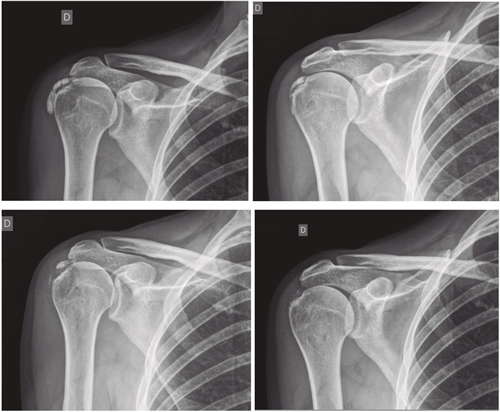

Resultados: Edad media: 54,6 años (n = 138); mujer (73,1 %; n = 101); proporción mujer/hombre 3: 1; tendón supraespinoso (94,6 %; n = 124); subescapular (5,4 %; n = 14); hombro izquierdo (55,1 %; n = 76), hombro derecho (44,9 %; n = 62); bilateral 1,4 % (n = 2); diestros 96,3 % (n = 133); antecedentes personales: tabaquismo (19,5 %; n = 27), diabetes (7,2 %; n = 10). El tiempo de enfermedad promedio fue de 6,08 meses. Dolor agudo-subagudo (menos de 3 meses) 47,1 %; (n = 65), dolor crónico (más de 3 meses) 52,9 % (n = 73). Tipo radiológico: formativo 75,3 % (n = 104), resortivo 24,7 % (n = 34). Número promedio de sesiones: 20. Complicaciones del tratamiento 2,8 % (n = 4): intolerancia/eritema/quemadura. Ocupación: administrativo 39,8 % (n = 55), trabajos manuales 60,2 % (n = 83). El dolor inicial EVA de 7,3 puntos disminuyó significativamente (p = 0,0000) después del tratamiento a 2,7. El tamaño promedio inicial de las calcificaciones fue de 10,7 mm y disminuyó significativamente (p = 0,0000) después del tratamiento a 3,8 mm. Cambio de calcificación: tasa de éxito/curación 55,7 % (n = 77), tasa de mejora 20,2 % (n = 28); tasa de fracaso del 23,9 % (n = 33). La limitación funcional disminuyó de un 10,8 % a un 2,1 %.

Figura 1